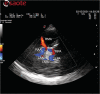

Aims and methods: We describe the ability of TCCS to directly and accurately image, in a 77-year-old woman hospitalised for septic shock and coma, a suprasellar meningioma with a spatial resolution very similar to CT.

Results: The meningioma was clearly visualised as a roundish mass, with well-defined borders, heterogeneously hyperechogenic compared with the surrounding brain structures; multiple intralesional calcifications were detectable as highly echogenic spots. Latero-lateral and antero-posterior diameters were well measurable.